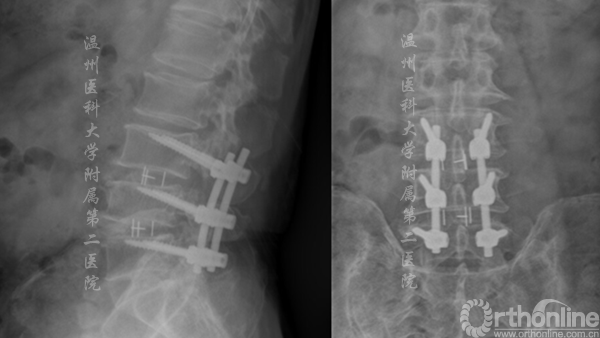

术后X线显示CBT螺钉未松脱、断裂,螺钉位置良好

术后X线资料(左侧)及术后切口对比(右侧)